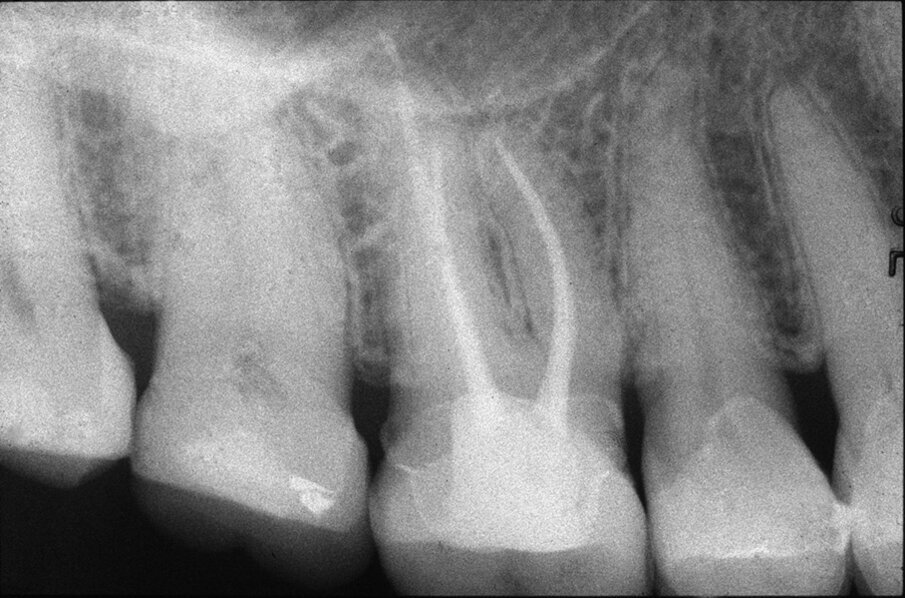

Queste perforazioni possono avvenire nel corso della strumentazione di canali curvi, per l’esecuzione del cosiddetto “trasporto esterno” del forame apicale. Una volta eseguita la perforazione, se l’operatore riesce a ritrovare e preparare il canale originale (con l’utilizzo di strumenti sottili e precurvati, molta irrigazione e soprattutto molta pazienza), il danno provocato dalla perforazione sarà minimo in quanto, soprattutto se la perforazione è piccola, si comporterà come un piccolo canale laterale che sarà facilmente otturato. Se invece il canale originale è rimasto intasato dai detriti di fango dentinale e gli strumenti ogni volta ripercorrono il cammino della perforazione, in tale caso il canale deve essere otturato con le metodiche tradizionali e successivamente l’apice contenente la porzione non trattata del canale radicolare deve essere rimosso per via chirurgica, soprattutto se stiamo trattando un dente necrotico o se siamo di fronte ad un ritrattamento (Figg. 1a-1e).

Le perforazioni del terzo medio avvengono nella maggior parte dei casi durante la preparazione della cavità d’accesso o, più spesso, durante le fasi di detersione e sagomatura o infine durante la preparazione dello spazio per un perno con l’utilizzo di frese tipo Largo, Peeso, Gates Glidden o simili (Figg. 2a-2f).